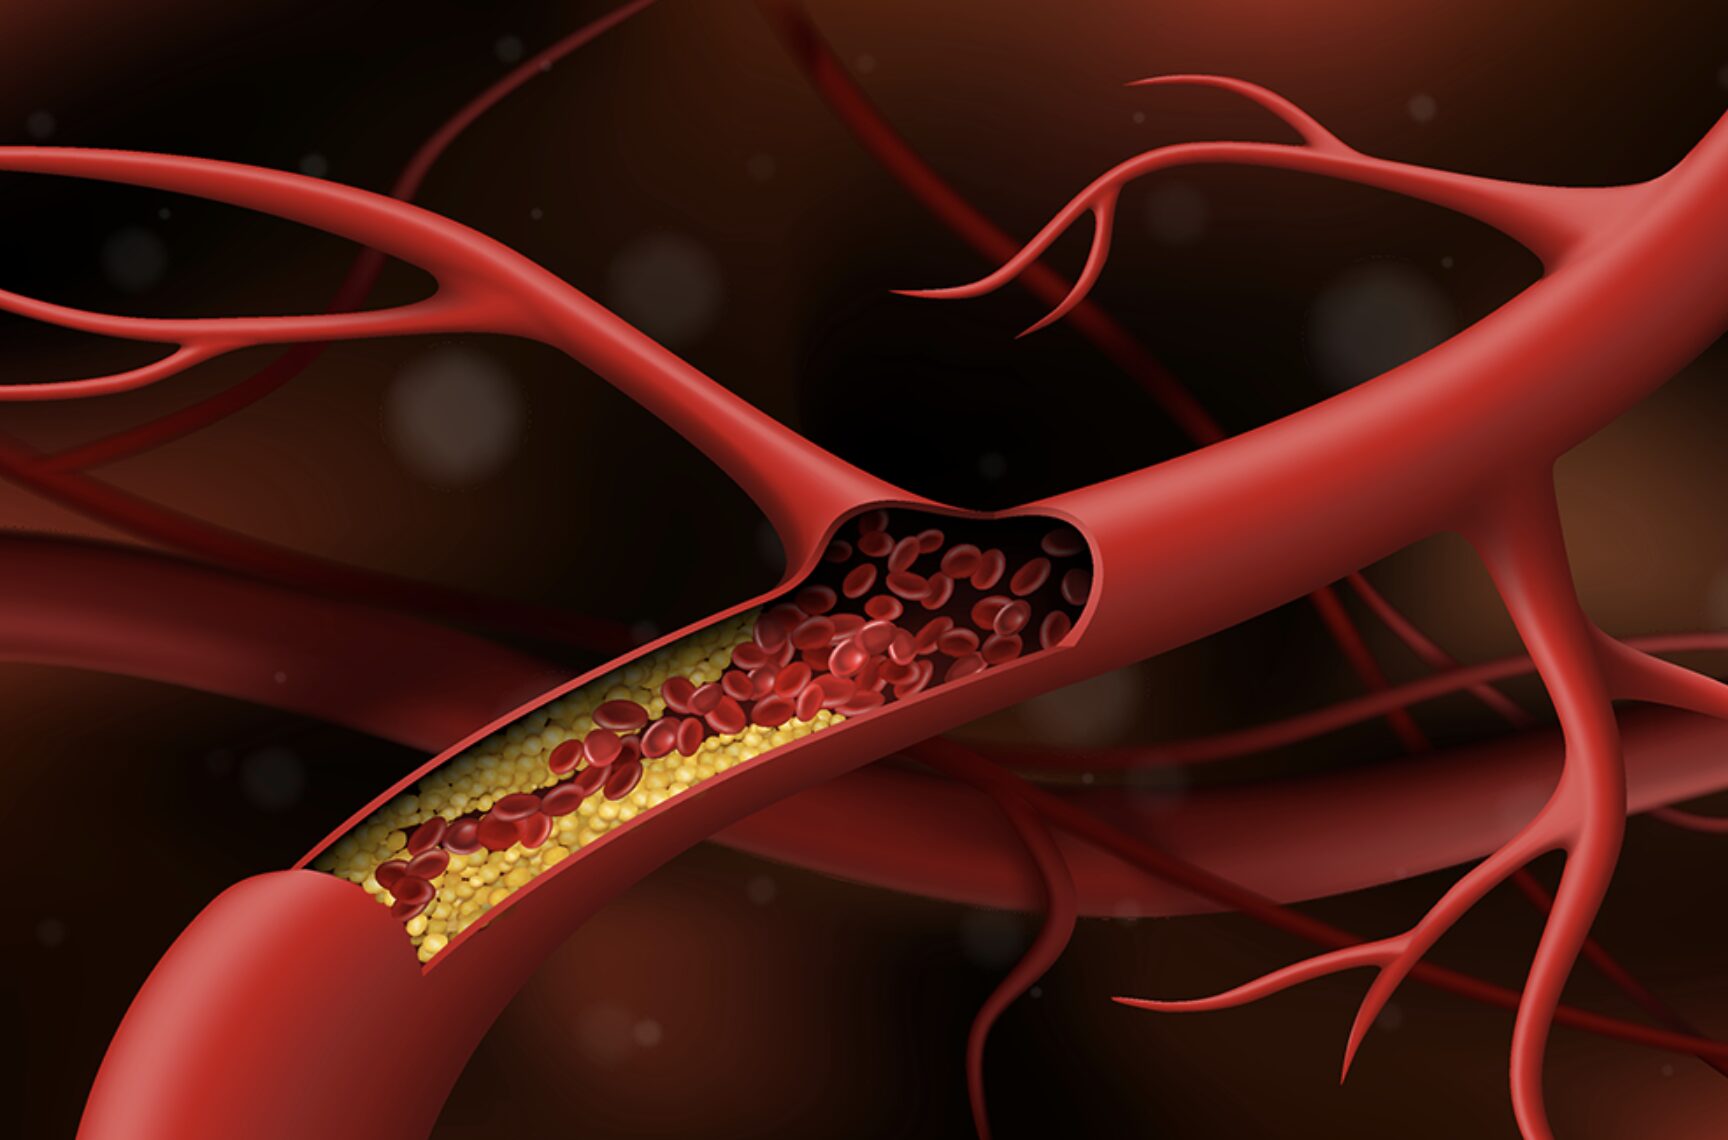

Tối ưu điều trị hẹp động mạch nội sọ: Khi nội khoa đi đến giới hạn, can thiệp là lựa chọn cần thiết

Tại hội nghị khoa học Stroke Intervention School 2025, TS.BS Trần Chí Cường – Chủ tịch Hội Thần kinh Can thiệp Việt Nam, Giám đốc chuyên môn Bệnh viện Đa khoa Quốc tế S.I.S Cần Thơ đã mang đến phần báo cáo đặc biệt, tổng hợp hàng loạt ca bệnh điển hình trong điều trị hẹp động mạch nội sọ. Không chỉ củng cố vai trò nền tảng của điều trị nội khoa, bác sĩ còn thẳng thắn chỉ ra ranh giới giữa hiệu quả và thất bại, nơi can thiệp trở thành lựa chọn mang tính cứu cánh.

Điều trị toàn diện – Giải pháp then chốt giúp ngăn ngừa đột quỵ tái phát

Tại Hội nghị khoa học Stroke Intervention School 2025, GS.TS Trương Quang Bình – Chủ tịch Phân hội Xơ vữa động mạch Việt Nam nhấn mạnh vai trò của điều trị toàn diện sau đột quỵ, trong đó 4 trụ cột kiểm soát huyết áp, LDL-cholesterol, nguy cơ huyết khối và đường huyết là yếu tố quyết định trong ngăn ngừa tái phát, vốn chiếm tỷ lệ tới 10% trong năm đầu sau đột quỵ tại Việt Nam.